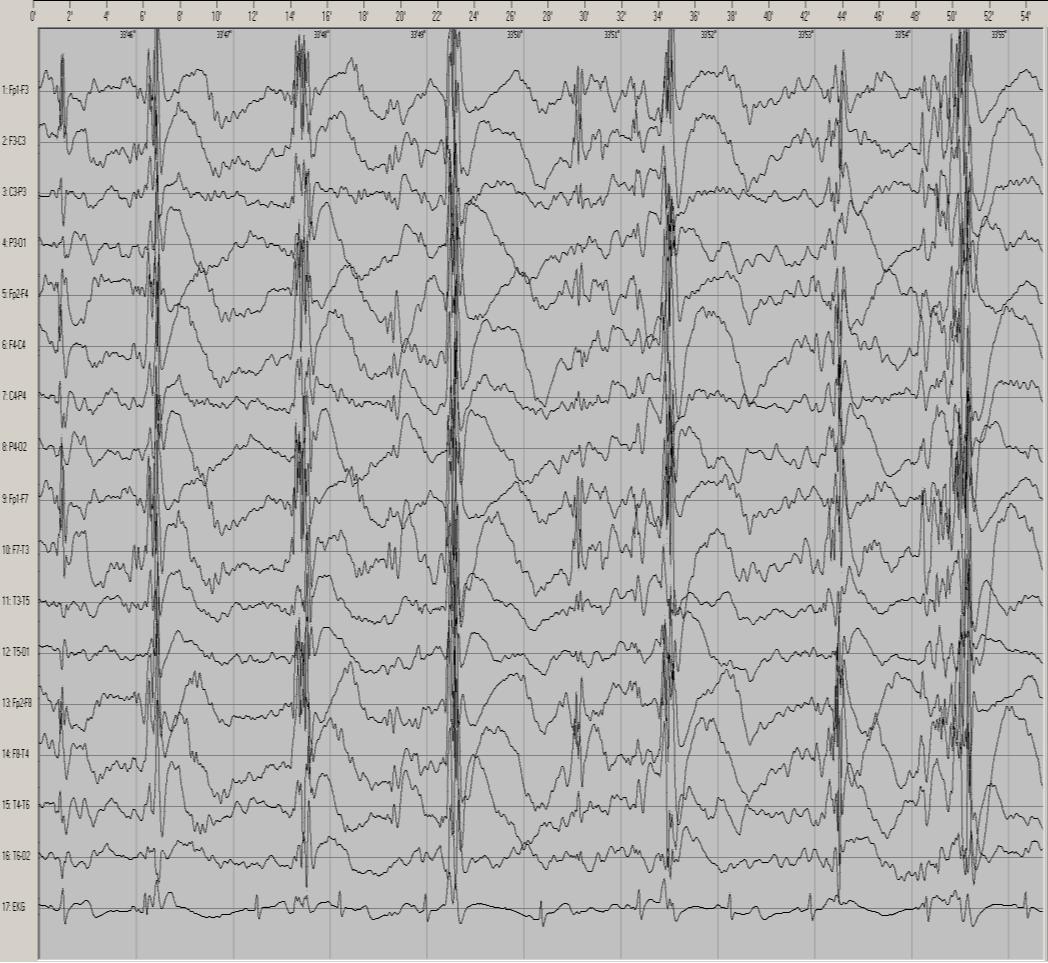

Poniższy śródnapadowy zapis czynności bioelektrycznej mózgu wykonano u 12-letniego pacjenta: W czasie tego badania zarejestrowano następujący typ napadów padaczkowych: